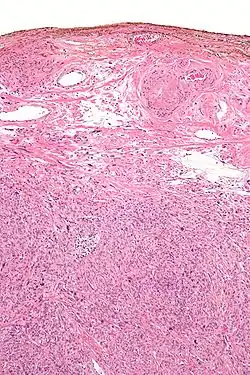

Micrograph showing a silver nitrate (brown) marked surgical margin.

Silver salts have antiseptic properties. In 1881 Credé introduced a method known as Credé's prophylaxis, which used of dilute (2%) solutions of silver nitrate in newborn babies' eyes at birth to prevent contraction of gonorrhea from the mother, which could cause blindness via ophthalmia neonatorum. (Modern antibiotics are now used instead).[19][20][21][22]